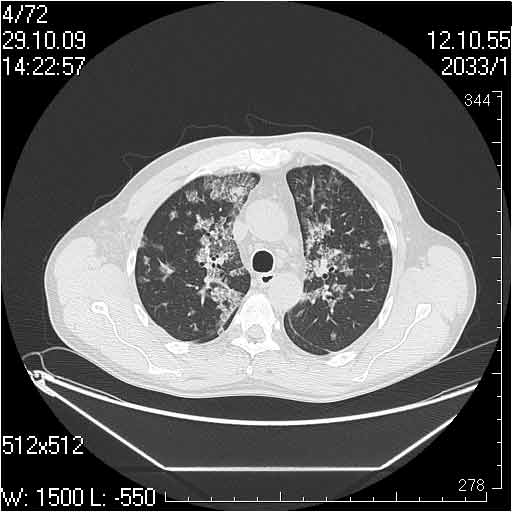

Случай №2

Мужчина 54 лет

Случай 2: картина патологических изменения довольно типична: GGOs & thickened interlobular septas = "crazy paving" sign. Наличие плотностей по типу матового стекла в сочетании с утолщением междолевых перегородок, даёт признак булыжной мостовой; на первом месте будет стоят диагноз альвеолярных протеиноз.